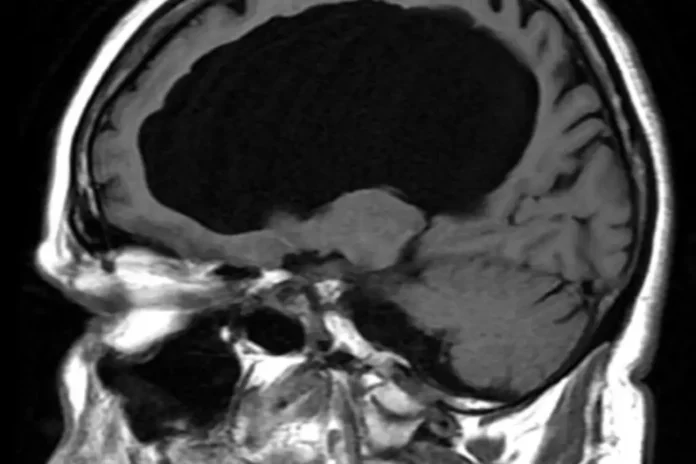

El estilo de vida, el estrés constante, la falta de sueño reparador, la mala alimentación y la alta exposición a la tecnología son factores que aumentan la probabilidad de padecer un infarto cerebral, y en México ese riesgo se ha elevado en poblaciones cada vez más jóvenes, alertó un especialista.

En el marco del Día Mundial del Cerebro, que se conmemora cada 22 de julio, el urgenciólogo Daniel Sánchez Arreola señaló que los infartos cerebrales en personas jóvenes han aumentado de forma preocupante en México y el mundo, debido a lo ya mencionado, pero también al incremento en el consumo de sustancia psicoactivas.

Explicó que en México, tan solo en 2024, se registraron 18.019 decesos por enfermedades cerebrovasculares, lo que posicionó a estas condiciones como la séptima causa de muerte a nivel nacional.

Además, de acuerdo con la Secretaría de Salud, cada año se registran 170.000 casos de infarto cerebrovascular y aunque el mayor número de fallecimientos se han registrado en personas mayores de 65 años, ahora los casos se presentan a edades menores.

«Hace 10 años estas enfermedades eran características de población de más de 60 o 65 años. Pero ahora, con 45 años ya es frecuente que las personas padezcan enfermedades crónicas como hipertensión o diabetes, que pueden ser la antesala a un infarto cerebral”, enfatizó.

El especialista dijo que es importante tomar medidas de prevención y cuidado en todas las edades, ya que quienes sobreviven a estos eventos es muy factible que presenten algún tipo de discapacidad dependiendo de la zona del cerebro que haya sido afectada